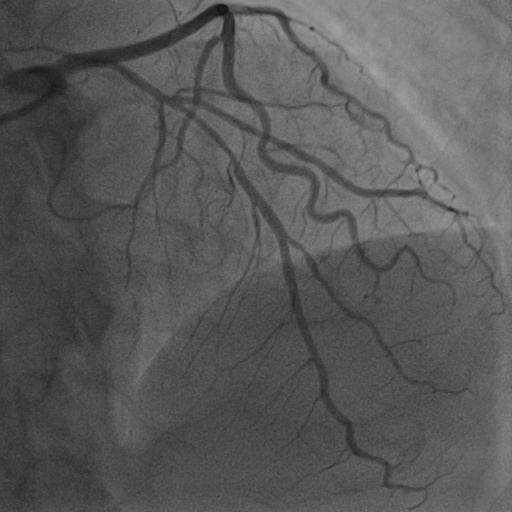

4.1 XACV Dataset

We collect 111 complete records of coronary artery X-ray videos, encompassing the injection, flow through the blood vessels around the heart, and dissipation of the contrast agent. Subsequently, we establish the XACV (X-ray Angiography Coronary Video) dataset. Each video consists of varying numbers of high-resolution coronary artery X-ray images. We invite experienced radiologists to annotate the vascular regions, focusing on one or two frames where the contrast agent is most prominent in each video. The XCAD dataset contains only a single image, and the CADICA video dataset does not provide corresponding ground truth. Therefore, in the following experiments, we conduct all the analyses on our collected XACV dataset and the corresponding GT for each sequence. In Figure 5, we show that compared to other publicly available datasets, XCAD [33] and CADICA [19], our dataset exhibits finer annotations in the vascular regions, providing an advantage for future related tasks. The development and use of our dataset have been approved by our institution’s IRB.